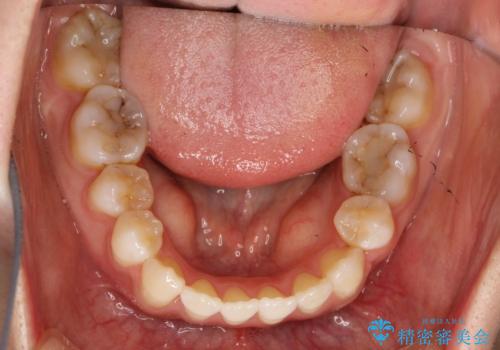

ガタガタがなくなり、上下の前歯が接触すようになり、見た目とともに咬みやすくすることができました。